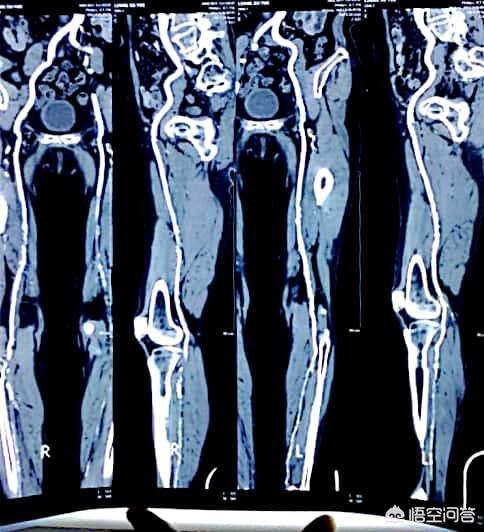

L'incidence du diabète est aujourd'hui vraiment très élevée, généralement chez les plus de cinquante ans, l'examen physique de dix personnes révèle au moins l'une des trois anomalies (taux élevé de graisse dans le sang, tension artérielle élevée, taux élevé de sucre dans le sang), et certaines présentent même les trois anomalies en même temps. L'apparition des trois hyperglycémies et le rythme de vie moderne ainsi que les habitudes alimentaires des gens sont étroitement liés, la figure suivante montre un patient diabétique présentant une plaque vasculaire au niveau des membres inférieurs :